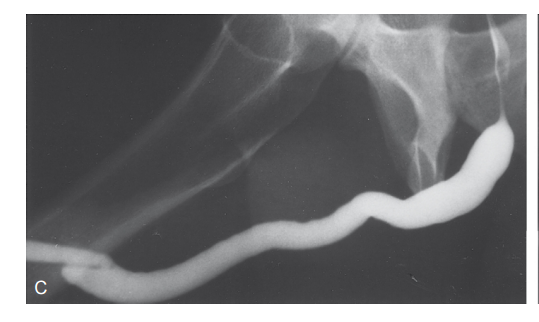

• Уретрографія – рентгенологічне дослідження з контрастом.